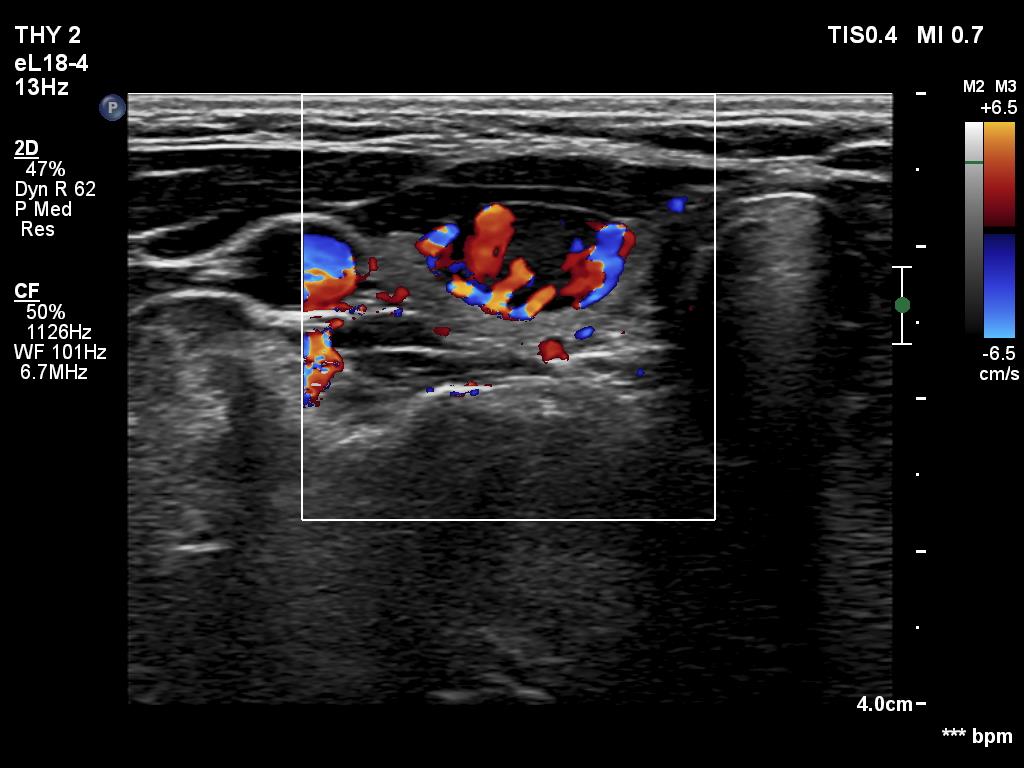

Ultrasonography. The thyroid was echonormal. There was a moderately hypoechoic nodule in the ventral part of the right lobe. This lesion has regular, sharp margins and presented signs of a possible extrathyroidal spread. The intranodular vascularity was increased. The left lobe had a tiny, minimally hypoechoic lesion. The largest diameter was 7 mm. The lesion had both echogenic lines and granules, a pattern corresponding either to connective tissue or back wall figure. The lesion had neither halo nor perinodular blood flow.

1. The nodule in the right lobe is remarkable because of the hypoechogenicity, the increased vascularity and because it shows sing of a possible extrathyroidal spread.